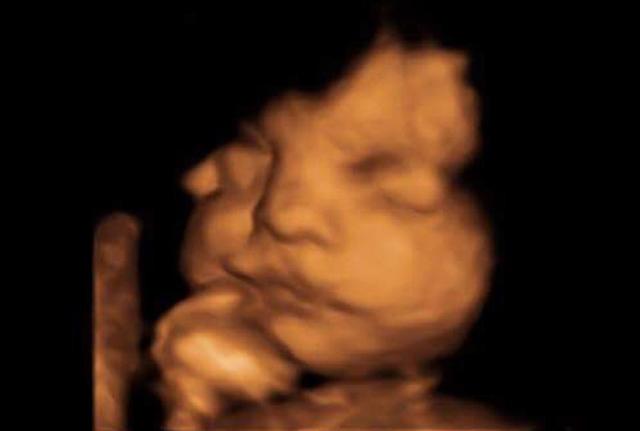

Một số hình ảnh siêu âm trước đây của cậu bé.